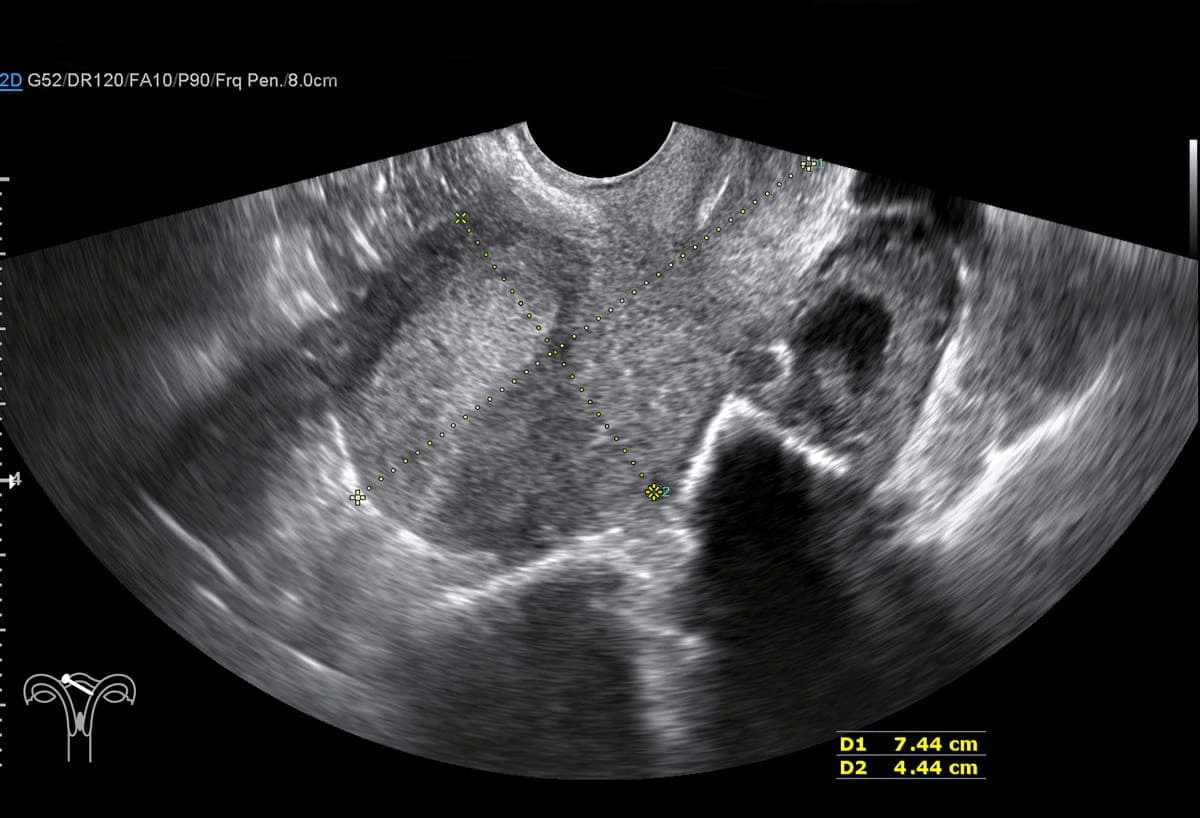

O que é reserva ovariana?

Reserva Ovariana está relacionada à quantidade de óvulos disponíveis para fertilização, acompanhá-la pode mudar totalmente o seu futuro...

Baixa reserva ovariana: O que fazer e a quais tratamentos recorrer

Ainda que seja inevitável, a baixa reserva ovariana pode ser contornada; no conteúdo de hoje, veja como proceder em um quadro clínico como...